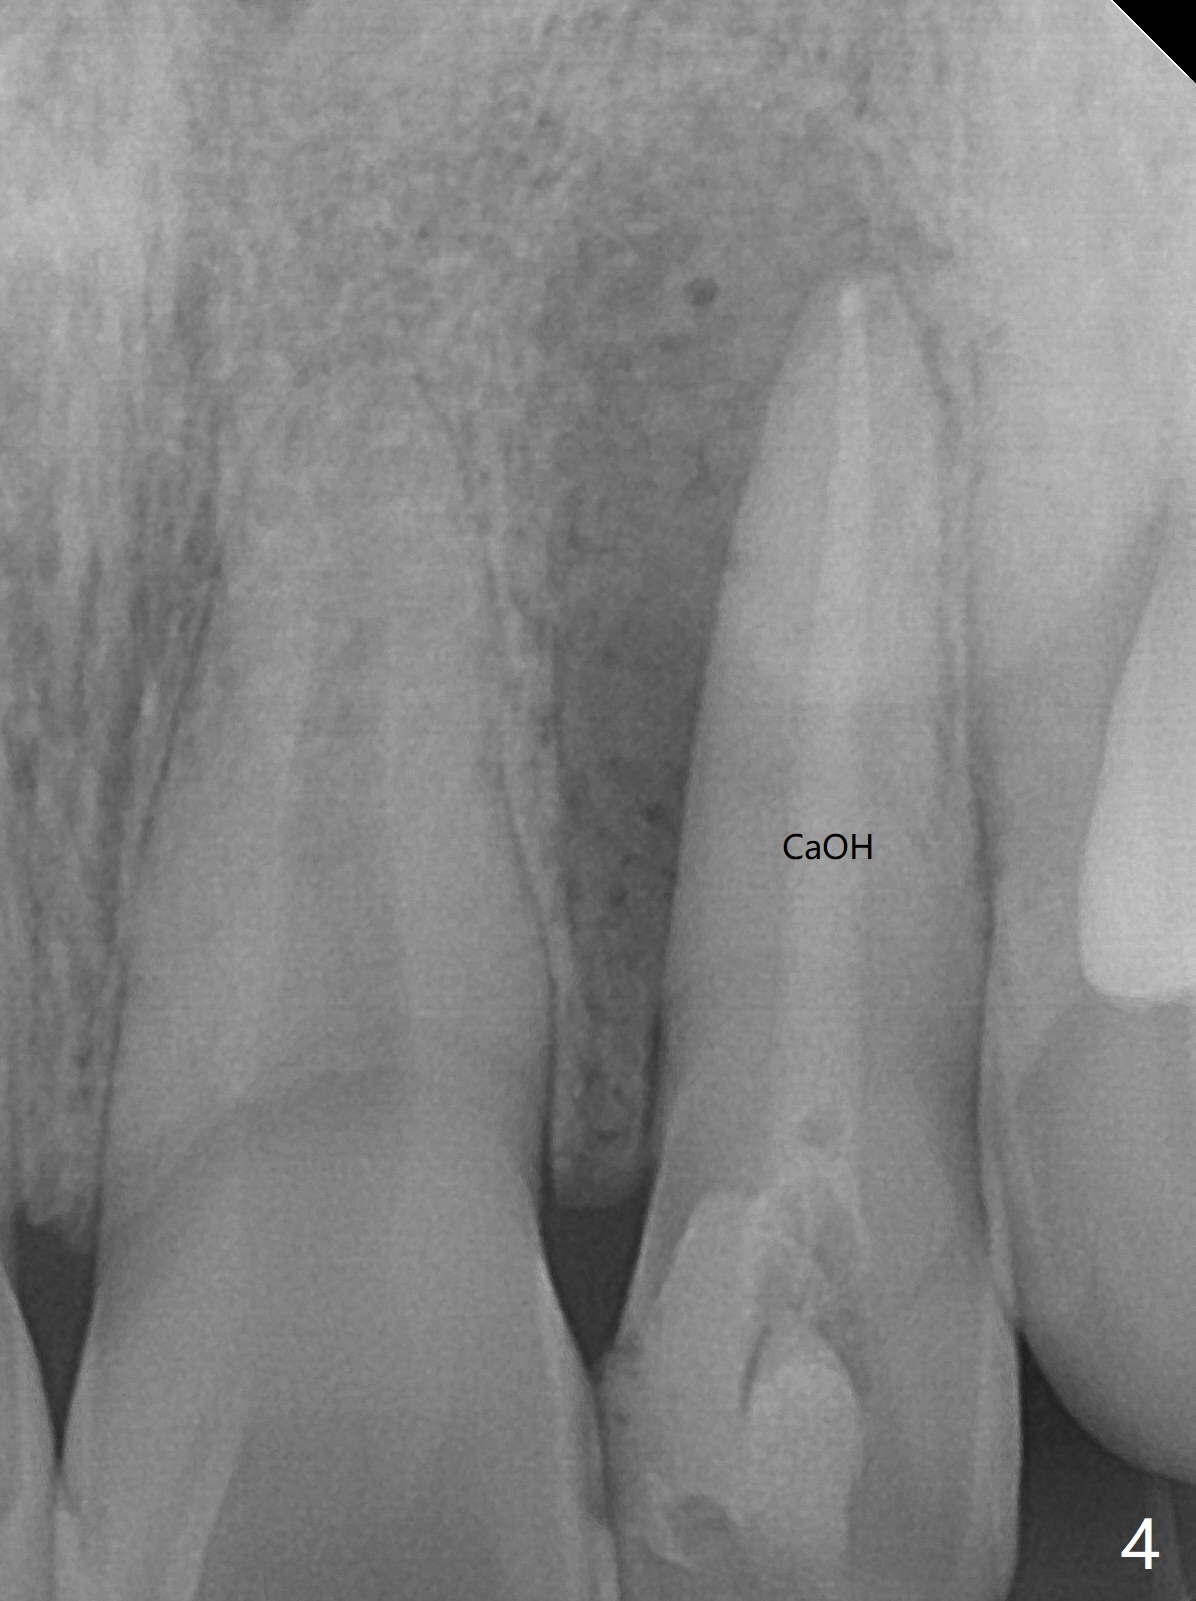

21岁女左上侧切牙根管治疗在别的诊所完成后出现瘘道(图一),近中阴影相当大(图二),应该如何处理?单独重做根管治疗足够吗?牙齿似乎没有松动,牙周袋正常,龋齿易感性高。牙列完整,仿佛没有咬合创伤迹象。可能由于经济问题,家长迟迟不带她去看专家。上个月我开始重做(图三:40/.04),能一次完成治疗吗?保险起见,放置氢氧化钙糊剂(图四)。一个月后病人回来,瘘道减小(图五),多次根管冲洗后,放置主牙胶尖(图六:40/.04),我当时在想根侧方阴影这么大,是不是有侧枝根管?如果扩根完善,根充时可能显示!是吗?其实这是最后根尖片(图七),40/.04主牙胶尖加三个fine, fine accessory gutta percha,并没有显示侧枝根管。